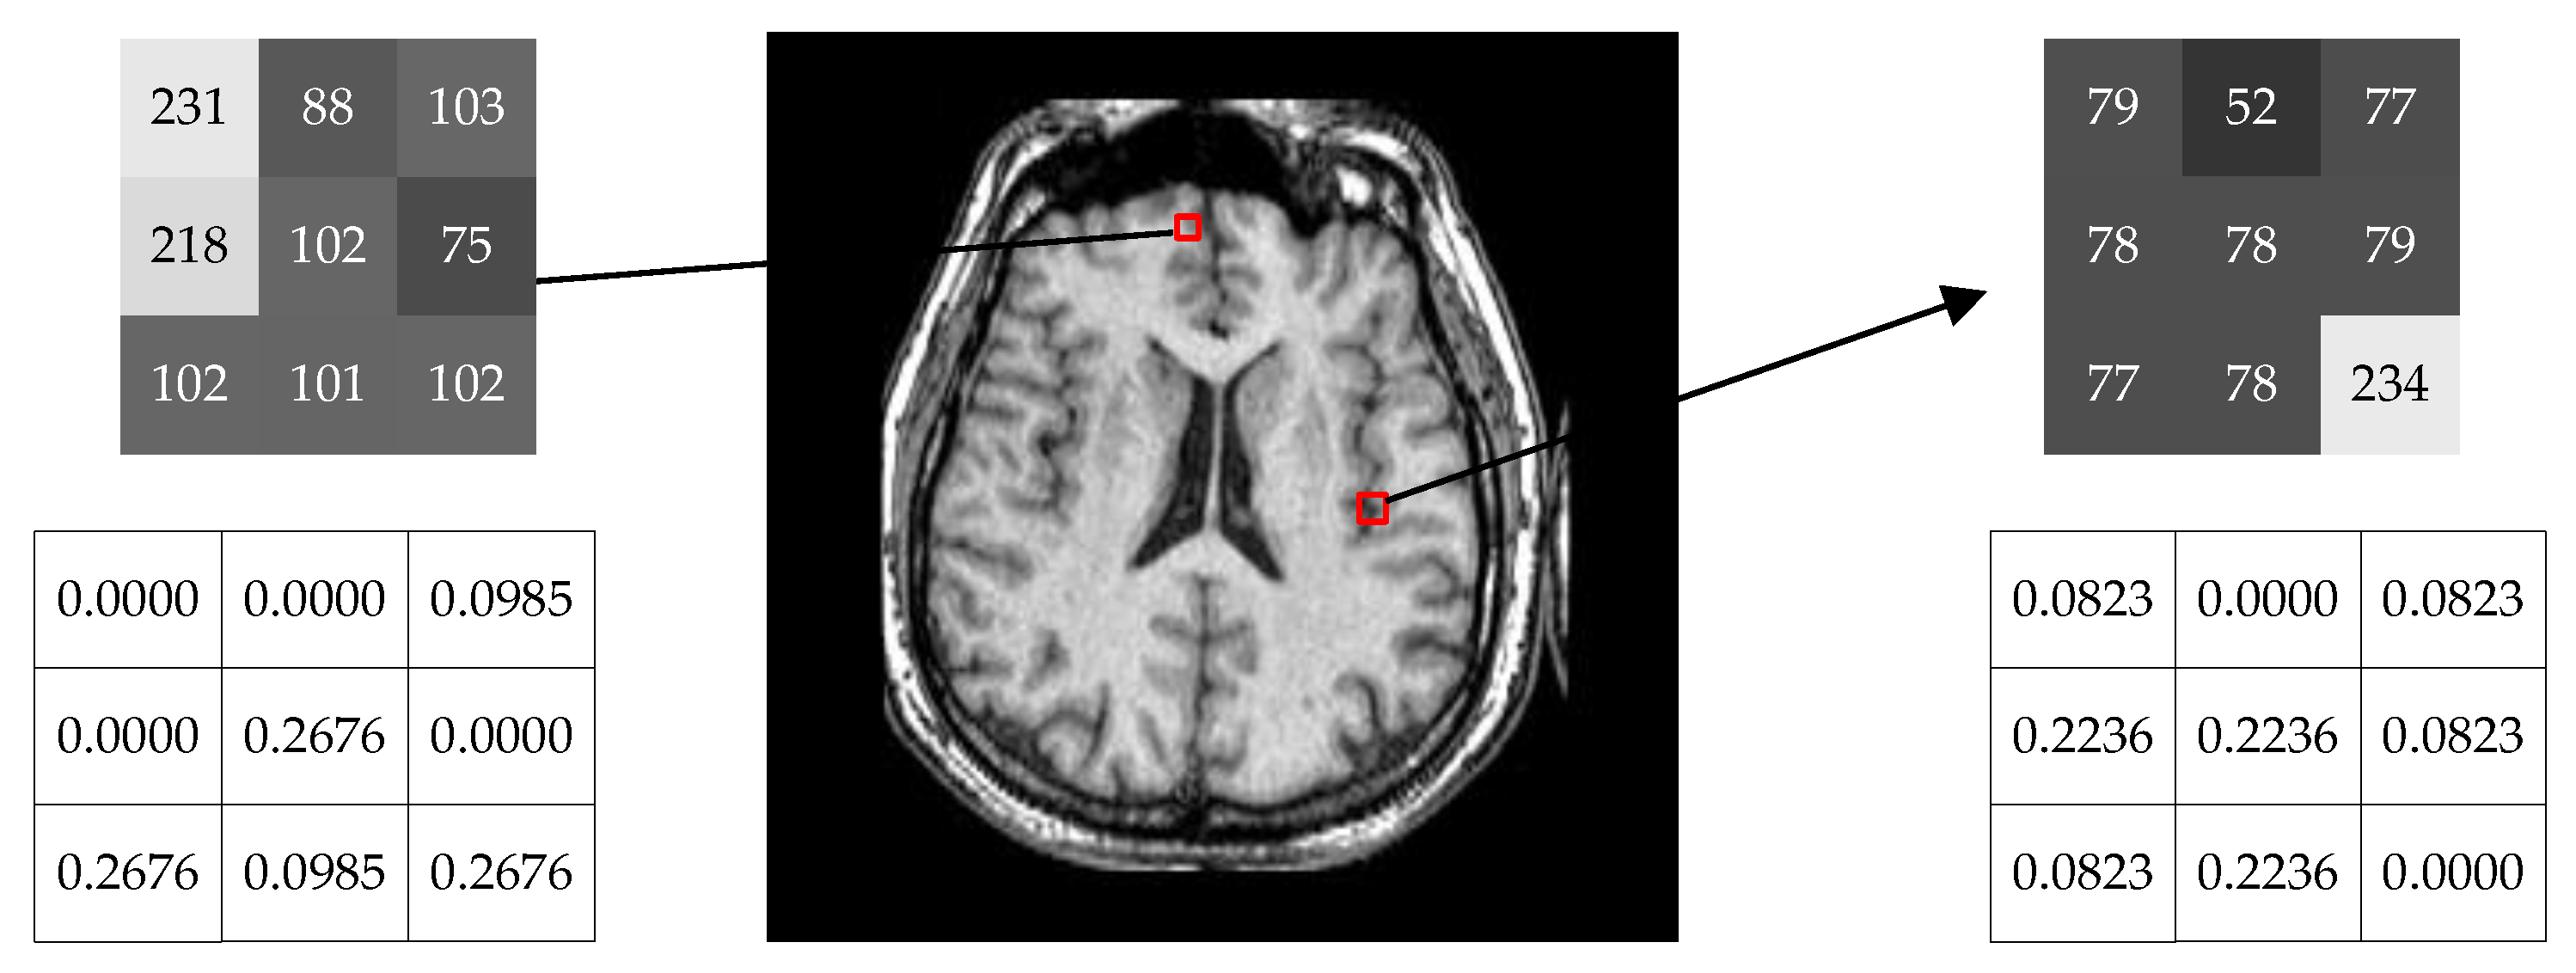

3.1. Weighted Measure with Neighborhood Information